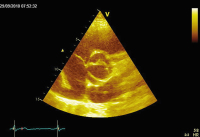

Abbildung

Echo

Abbildung 1: Bikuspide Aortenklappe

Keywords: AortenklappeEchoKardiologie